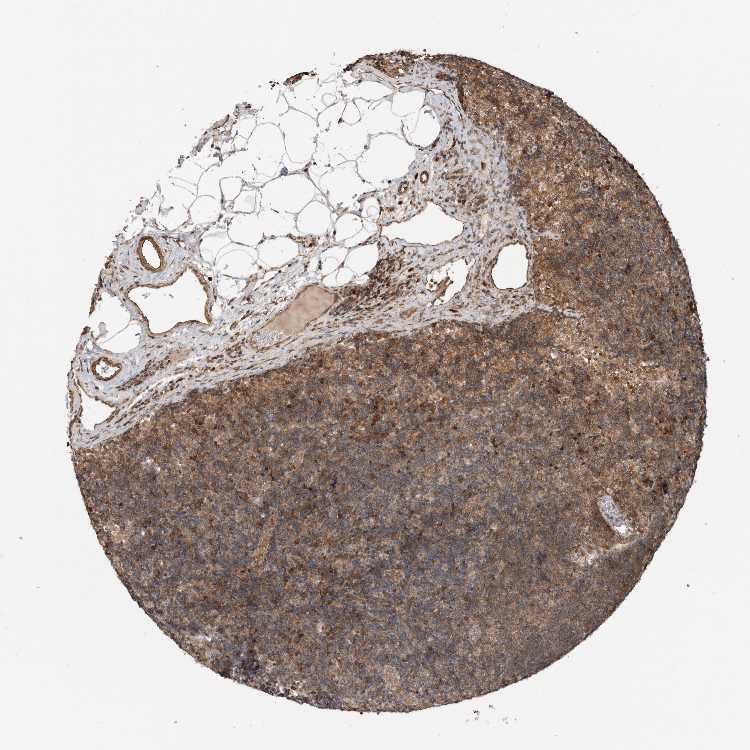

LYMPH NODE - Antibody stainingi

Antibody staining in the annotated cell types in the current human tissue is reported as not detected, low, medium, or high, based on conventional immunohistochemistry profiling in selected tissues. This score is based on the combination of the staining intensity and fraction of stained cells.

Each image is clickable and will lead to virtual microscopy that enables deeper exploration of all samples and also displays staining intensity scores, fraction scores and subcellular localization as well as patient and tissue information for each sample.

Antibody HPA007172Antibody CAB026471

Germinal center cells LowMedium

Non-germinal center cells Not detectedMedium